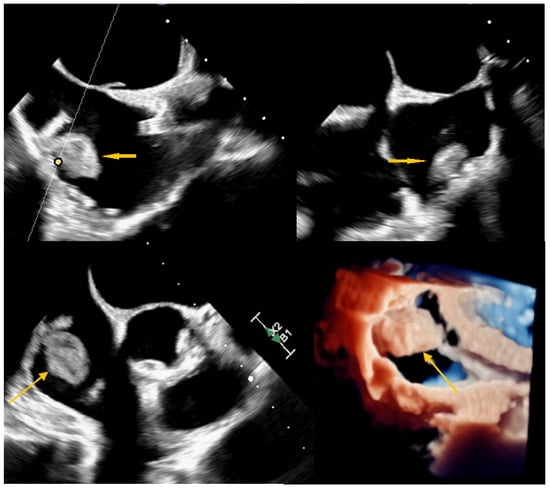

Echocardiography remains a vital part of the initial assessment and monitoring of oncological patients. It allows for proper treatment selection but can also reveal life-threatening complications, including impaired left ventricular function or thromboembolism. It can rarely detect intracardiac masses that require further investigation. In the presented case, a 51-year-old female patient with left-sided breast cancer, who had undergone neoadjuvant chemotherapy, was hospitalised due to a right atrial mass identified via routine transthoracic echocardiography (TTE). Initial anticoagulation therapy showed no clinical improvement. Follow-up TTE revealed a 12 × 19 mm hyperechogenic, mobile mass in the right atrium (RA). Computed tomography angiography (CTA) ruled out pulmonary embolism and revealed that the mass was located close to the tip of the vascular access port. Transoesophageal echocardiography showed that the lesion was not connected to the vascular port. Based on location and mobility, the lesion was most consistent with a cardiac myxoma. After the Heart Team made a decision, endovascular intervention using a vacuum-assisted device was performed without complications. Histopathological examination excluded thrombosis and myxoma, revealing a fibro-inflammatory lesion. A multimodality approach is necessary to assess RA masses. However, even an extensive evaluation could be misleading, so treatment options should always be subject to the Heart Team’s decision. Full article

Figure 1